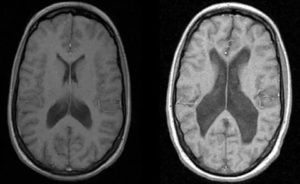

Ниже приведены примеры нейровизуализации больных с шизофренией при помощи МРТ технологий.

Пациент с шизофренией. Выполнена МРТ — ангиография у пациента выявлена трифуркация сосудов головного мозга. Одна из частых аномалий головного мозга, осложнением, которой является шизофрения.

На данном снимке фМРТ (функциональное МРТ) приведено сравнение активности мозга в норме и пациента с шизофренией, у которого также выявлена трифуркация артерии.

Слева — мозг здорового человека, справа — больного шизофренией (на снимке расширены боковые желудочки).